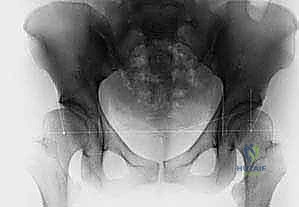

- الأشعة السينية (X-rays): تُستخدم للأطفال الأكبر من 6 أشهر بعد بدء تعظم رأس الفخذ.

خلال جميع هذه الخطوات، يتم استخدام جهاز الأشعة السينية المحمول (C-arm) للتأكد من أن المفصل في وضعه المثالي والتشريحي بنسبة 100%.